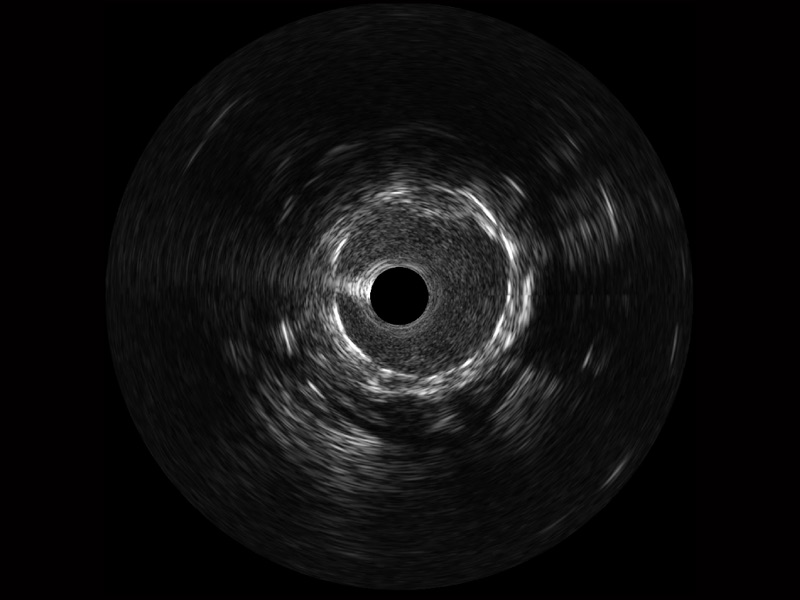

• 传统IVUS图像

对比传统IVUS导管成像,银河优越会宽频IVUS图像的近场支架梁显影更细腻,远场中膜外血管仍清晰可辨,兼顾远中近,兼顾分辨力与穿透深度